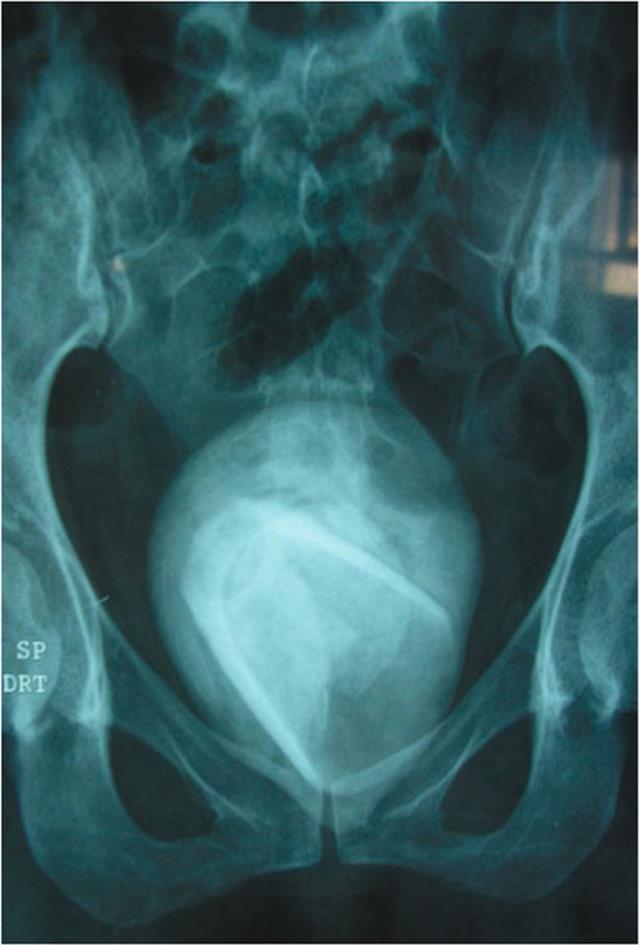

RÖNTGENDE ÇIKTI

Doktorlar tarafından çekilen röntgende, kadının mesanesinde bardak olduğu görüldü. Acil olarak ameliyata alınan kadının mesanesinden 8 cm büyüklüğünde su bardağı çıkarıldı.